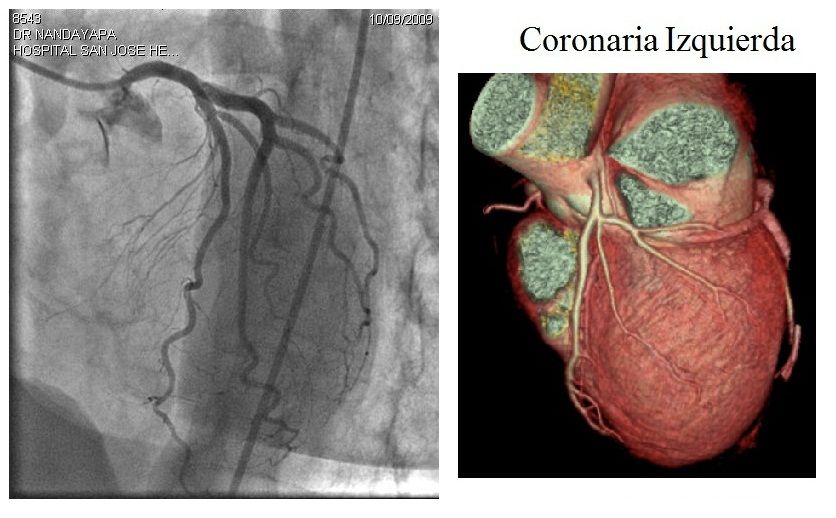

1. CATETERISMO CARDIACO :procedimiento complejo e invasivo que consiste en la introducciond e unos cateteres que se llevan hasta el corazon para valorar la anatomia del mismo y d elas arterias coronarias, asi como ver la funcion del corazon (cuanta sangre bombea), medir presiones de las cavidades cardiacas e incluso saber si hay alguna valvula alterada. permite ver si hay defectos congenitos como comunicaciones en el tabique auricular o ventricular.

1. ANGIOPLASTIA CORONARIA :es un procedimiento mendiante el cual a traves d eun cateter, se hace llegar un pequeño balon inflable a la seccion de la arteria obstruida. este balon al ser inflado, comprime la obstruccion contra las paredes de la arteria, abriendo paso a la sagre qeu circula por ella.

1. ANGIOTAC :estudio minimamente invasivo de las arterias de diferentes partes del cuerpo mediante la inyeccion de medio de contraste endovenoso. pueden estudiarsen las arterias cerebrales, carotidas, aorta o pulmonares. el sofware del equipo permite obtener imagenes en 3 dimensiones de ellas, se usa para el estudio de obstrucciones, aneurismas o trombo embolismo.